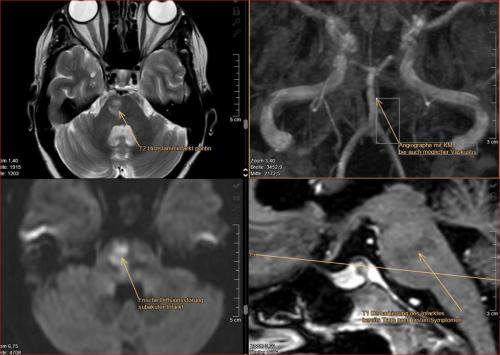

Aneurysma re. 7 mm Darstellung in einer DSA (digitalen Subtraktionsangiographie) links nur ein 2 mm „Baby-Aneurysma“ Im MRT war zuvor das linke Aneurysma aufgefallen, die Auflösung einer DSA ist technisch im MRT nicht erzielbar, beide A. liegen in der ACM Bifurkation jeweils, das re. Aneurysma wurde erfolgreich operiert, das linke Aneurysma wird kontrolliert.